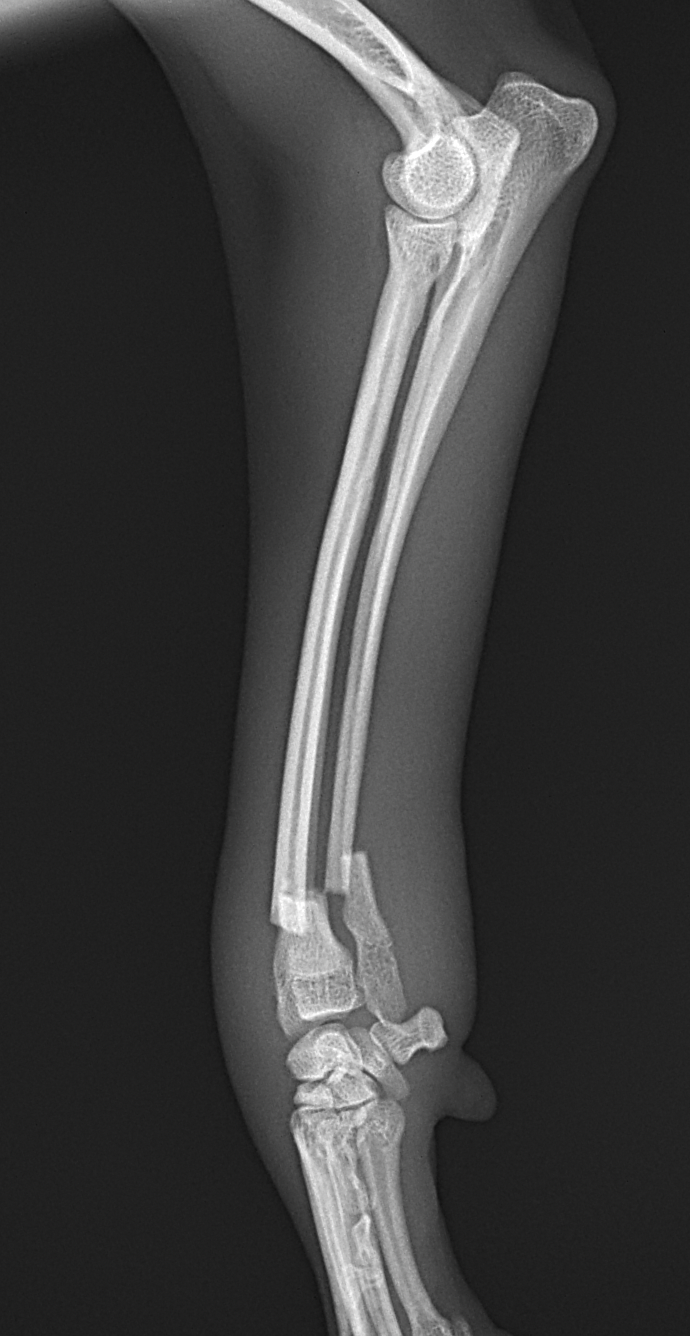

橈骨固定術 #248

小型犬が室内でジャンプして着地に失敗し、前肢を痛がり始めたとの事。かかりつけ医で橈尺骨遠位端骨折が確定されました。整復を目的に当院を受診されました。1.5 Titanium Locking Plateを用いて固定術を行いました。しばらく安静が必要です。